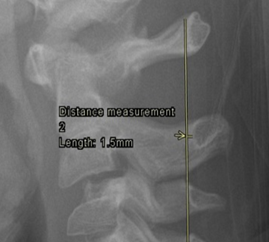

2. Pseudosubluxation of C2

Physiological anterior displacement of C2 on C3 is commonly seen in children, usually <7 years of age, less commonly in older children. It is most commonly seen at C2 on C3, but may less often be seen at C3 on C4. This finding is more pronounced in flexion and can present confusion in the presence of traumatic cervical injury .2 Utilization of Swischuk’s line is useful in differentiating pathological anterior cervical spine displacement from physiological displacement. This line is drawn from the anterior aspect of posterior arch of C1 to anterior aspect of posterior arch of C3 3 and should measure less than 2-mm. A measurement of greater than 2-mm indicates true subluxation. It is important to note that this line should only be used in the absence of other signs of instability and in the absence of prevertebral soft tissue swelling.